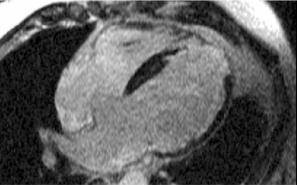

- Hallazgo típico: dilatación de las cavidades afectadas y su forma esferoidal, especialmente del ventrículo izquierdo.

- Las paredes están adelgazadas.

- Disminución difusa de la función contráctil.

Ecocardiografía 2D. Marcada dilatación de las cavidades cardíacas.